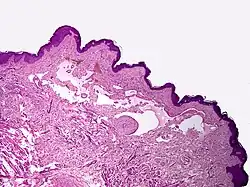

Microscopically, the vesicles in lymphangioma circumscriptum are greatly dilated lymph channels that cause the papillary dermis to expand. They may be associated with acanthosis and hyperkeratosis. There are many channels in the upper dermis which often extend to the subcutis (the deeper layer of the dermis, containing mostly fat and connective tissue). The deeper vessels have large calibers with thick walls which contain smooth muscle. The lumen is filled with lymphatic fluid, but often contains red blood cells, lymphocytes, macrophages, and neutrophils. The channels are lined with flat endothelial cells. The interstitium has many lymphoid cells and shows evidence of fibroplasia (the formation of fibrous tissue). Nodules (A small mass of tissue or aggregation of cells) in cavernous lymphangioma are large, irregular channels in the reticular dermis and subcutaneous tissue that are lined by a single layer of endothelial cells. Also an incomplete layer of smooth muscle also lines the walls of these channels. The stroma consists of loose connective tissue with a lot of inflammatory cells. These tumors usually penetrate muscle. Cystic hygroma is indistinguishable from cavernous lymphangiomas on histology.[7]